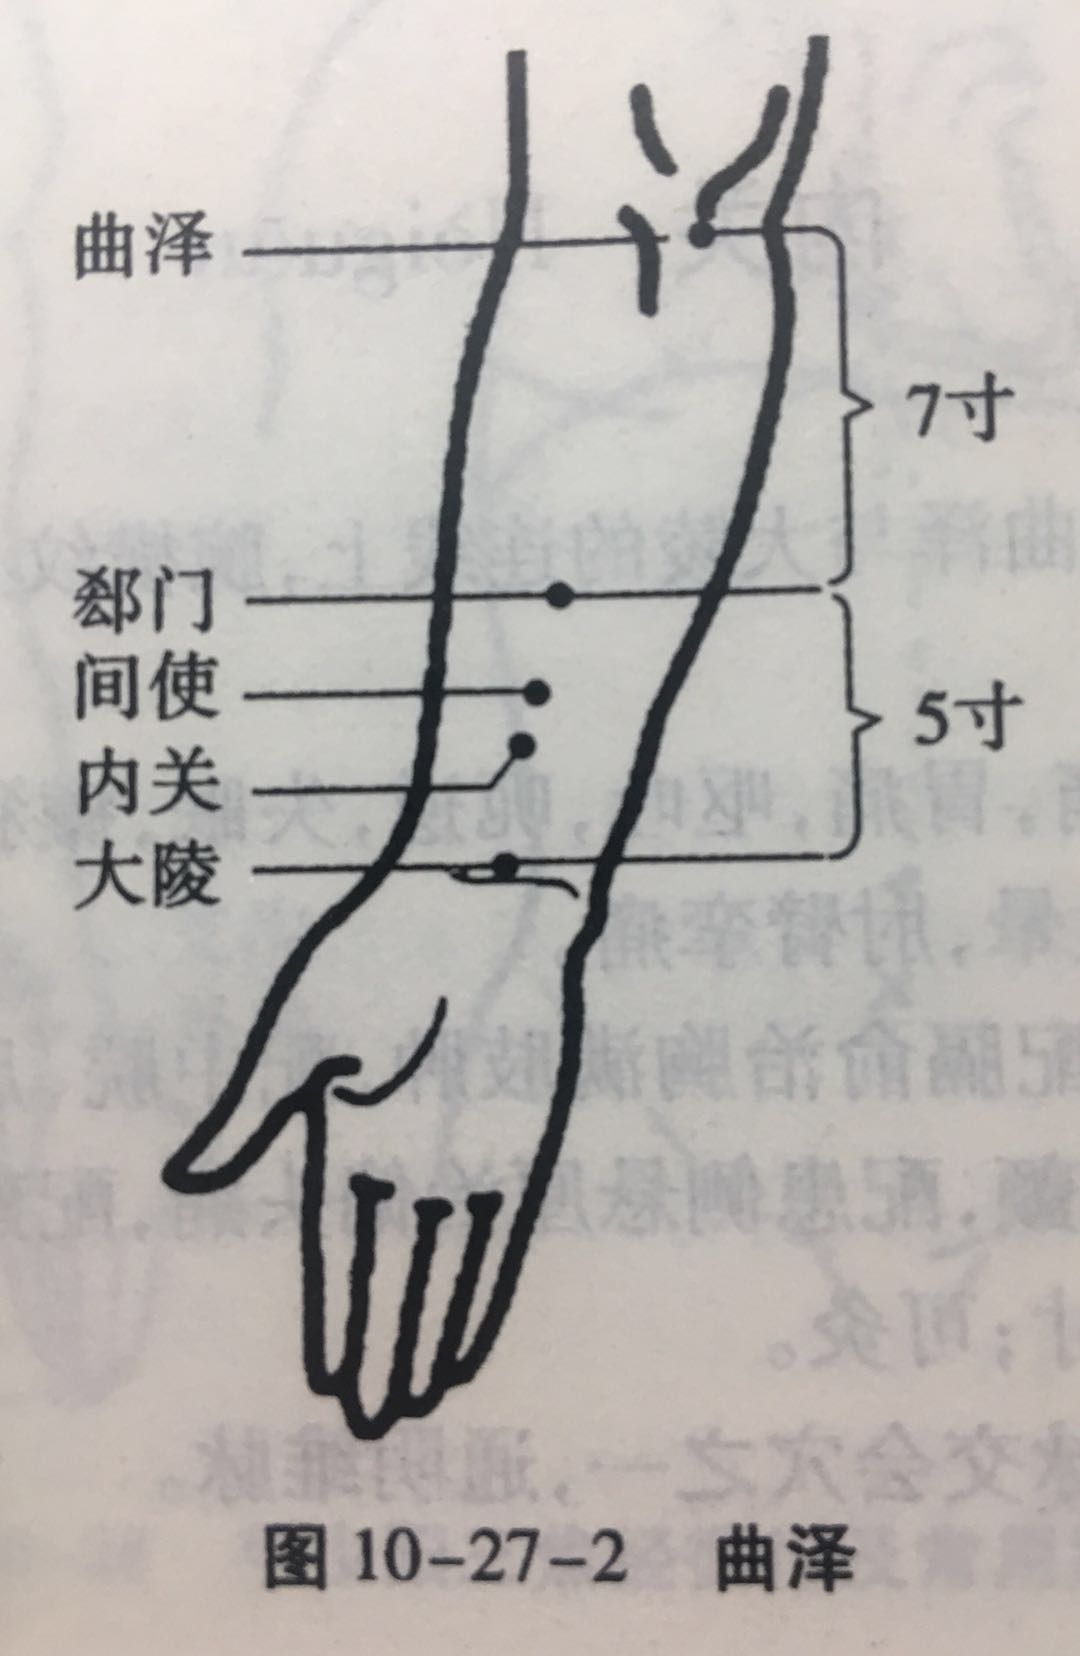

曲泽

【定位】 在肘横纹中,当肱二头肌腱的尺侧缘(图 10-27-2)。

【主治】 心痛,善惊,心悸,胃痛,呕吐,转筋,热病,烦躁,肘臂痛,上肢颤动,咳嗽。

【配伍】 配神门、鱼际治呕血,配内关、大陵治心胸痛,配大陵、心俞,厥阴俞治心悸、心痛,配少商、尺泽、曲池治疗肘臂挛急、肩臂痛。

【刺灸法】 直刺 0.8 ~ 1 寸,或者用三棱针点刺出血;可灸。

【附注】 心包络合穴。

郗(xī)门

【定位】 在前臂掌侧,当曲泽与大陵的连线上,腕横纹上 5 寸。

内关

【定位】 在前臂掌侧,当曲泽与大陵的连线上,腕横纹上 2 寸,掌长肌腱与桡侧腕屈肌腱之间(图 10-27-2)。